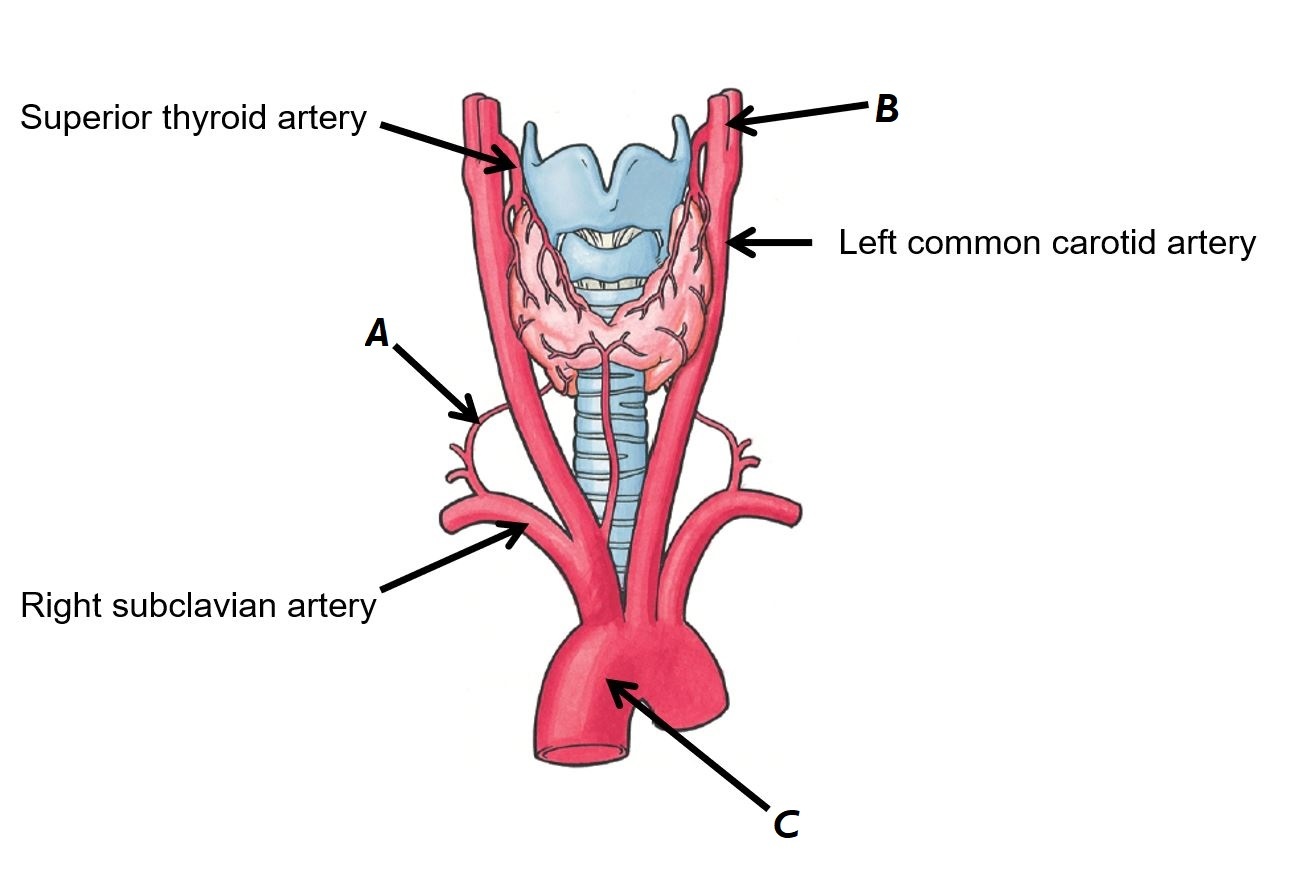

Name vessels A, B and C

A - Superior vena cava

B - Superior thyroid vein

C - Inferior thyroid vein

Name vessels A, B and C

A - Right inferior thyroid artery

B - Left external carotid artery

C - Arch of the aorta